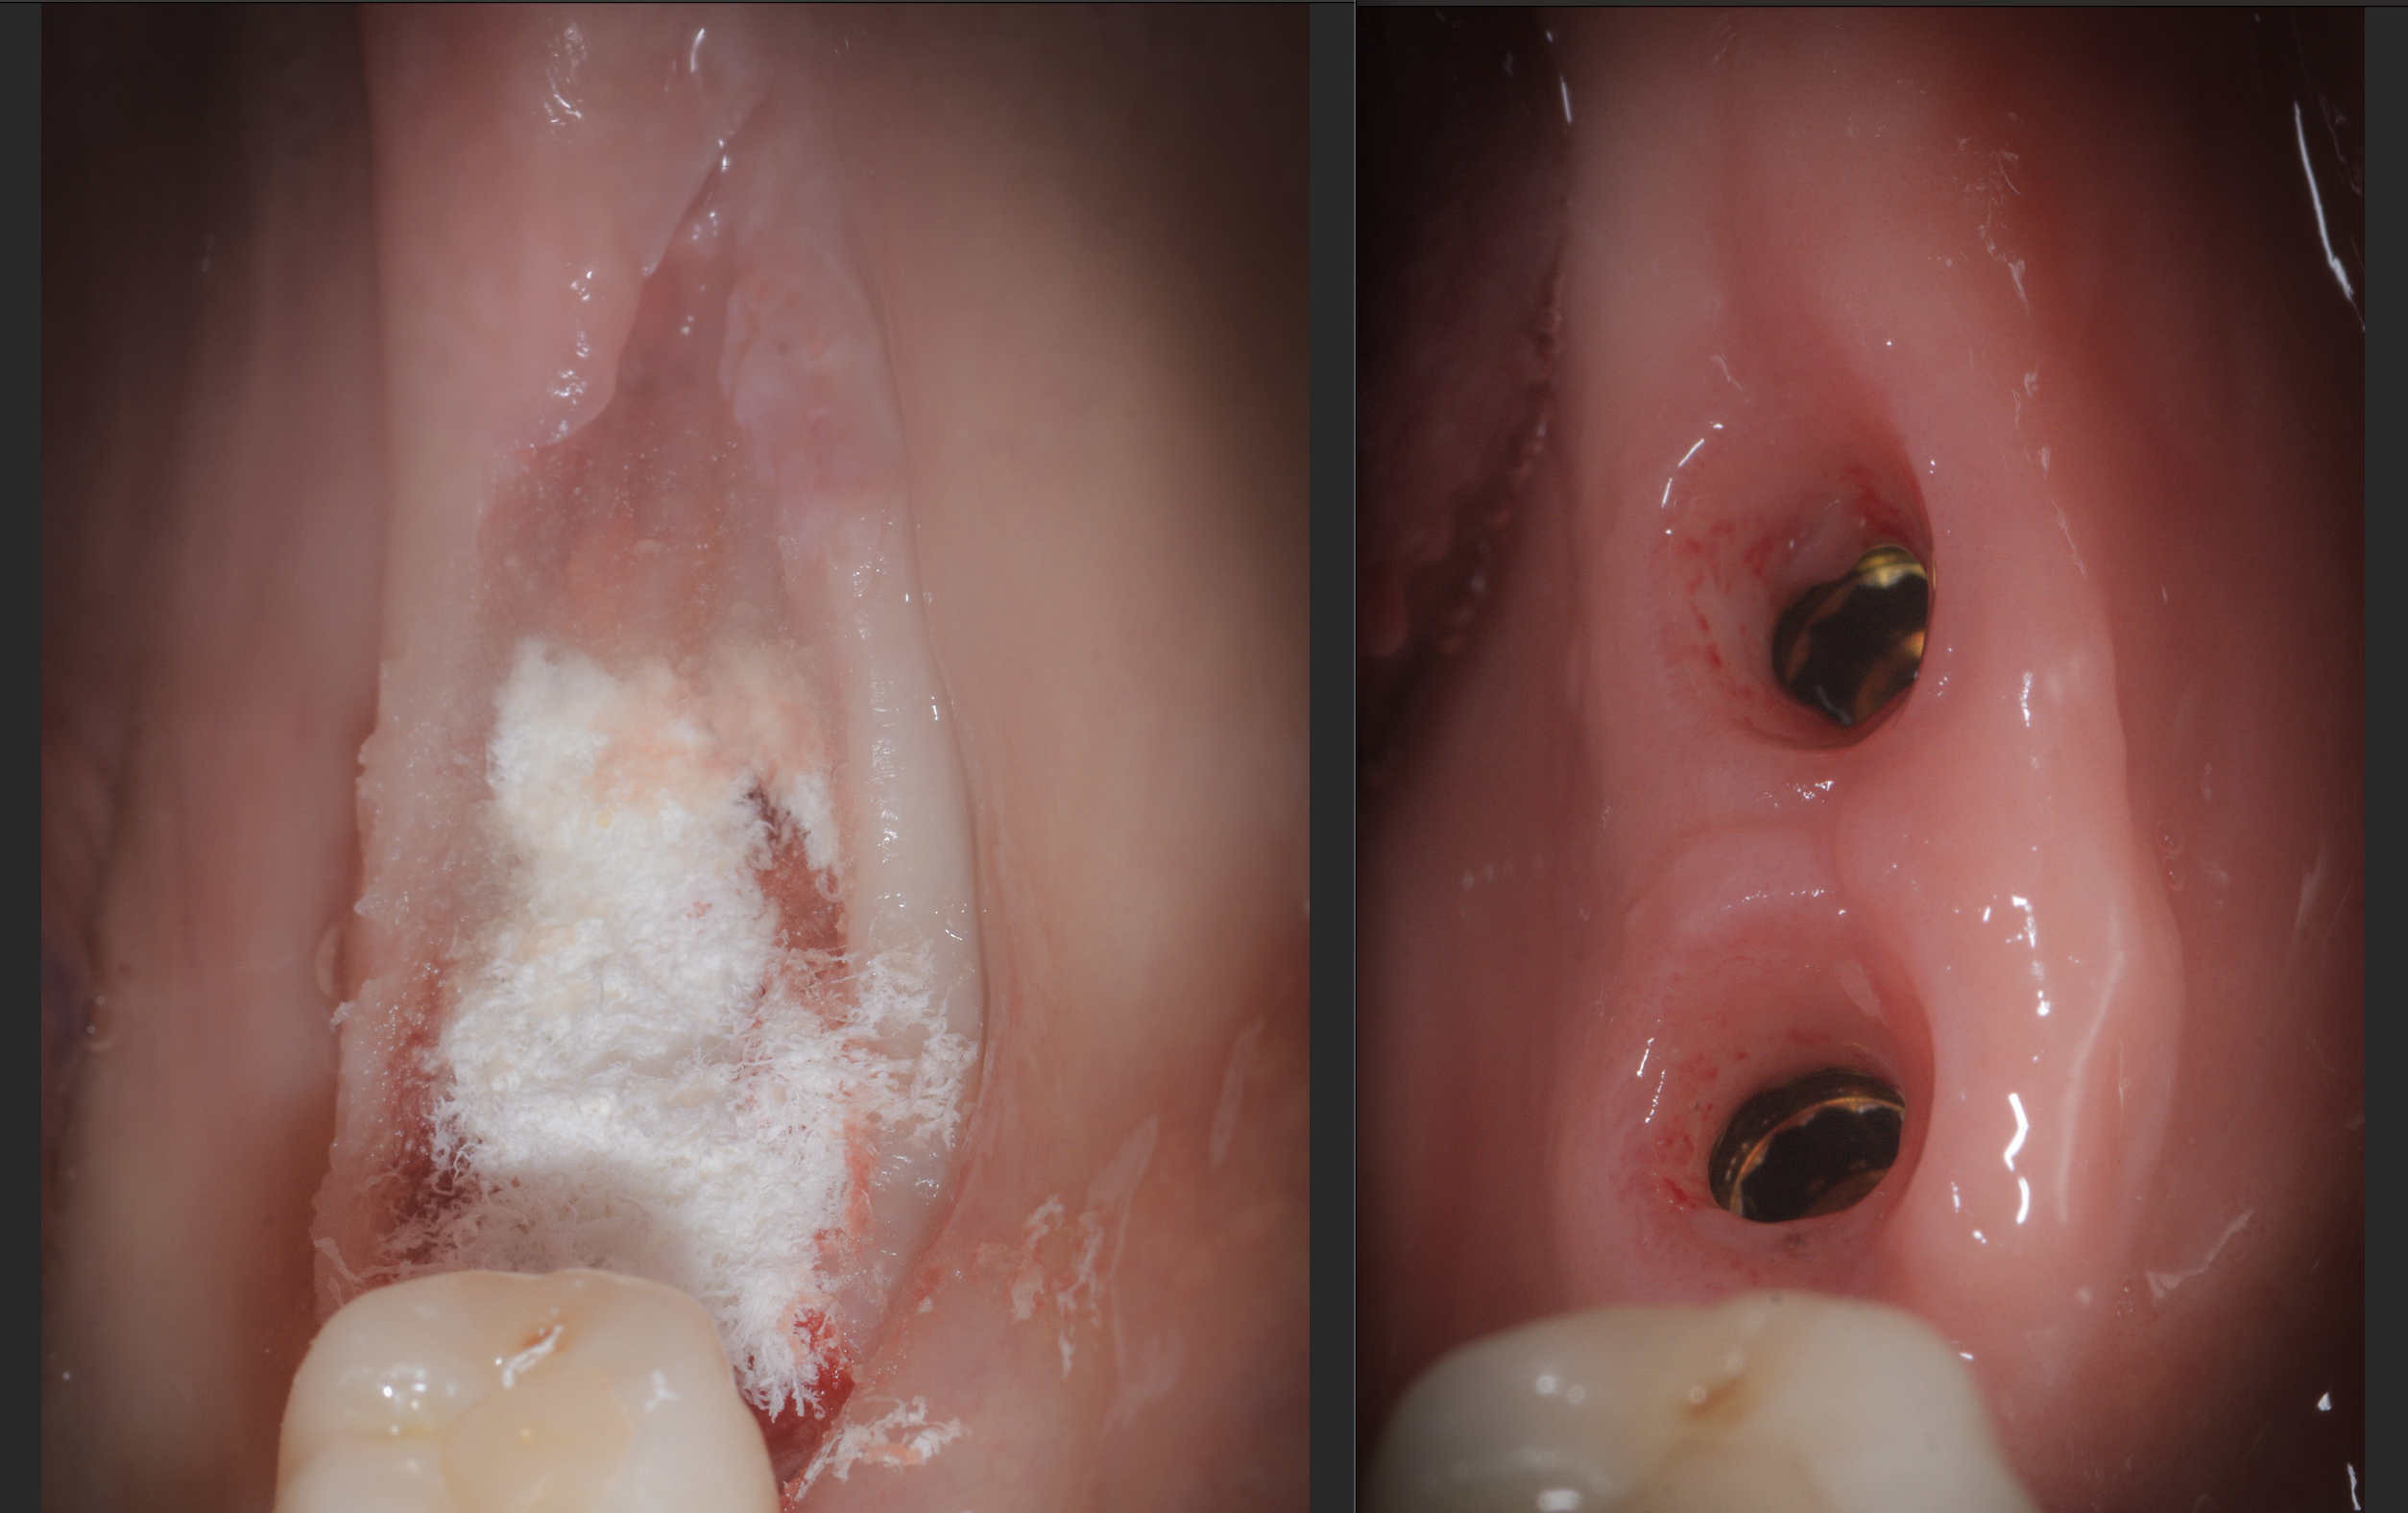

Il “bonebending” è una tecnica chirurgica innovativa per l’aumento osteo-mucoso, che consente di posizionare impianti con minori disagi per i pazienti e senza l’uso di biomateriali. Attraverso la migrazione cellulare, è possibile rigenerare tessuti e osso in modo naturale, garantendo risultati rapidi e una guarigione efficiente.

Il bonebending offre vantaggi rispetto alla rigenerazione ossea tradizionale, inclusa una minore necessità di innesti, procedure less invasive, risultati più rapidi, maggiore soddisfazione del paziente e un’espansione tridimensionale dell’osso alveolare. Queste caratteristiche migliorano l’efficacia delle procedure implantari, riducendo complicazioni e ottimizzando il recupero.